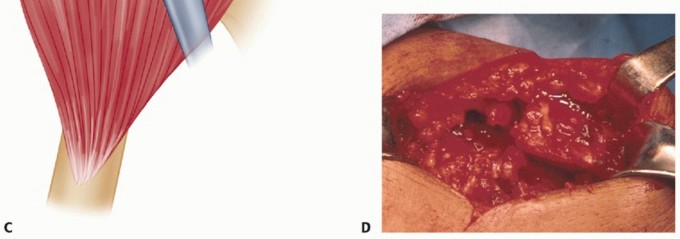

The bursa is incised, undermined, and reflected. The tear in the cuff can now be seen. The friable, avascular edges are trimmed with a sharp knife. This resection is minimal—only until healthy tendon is seen ( TECH FIG 4A ), not to bleeding tendon. This usually requires the removal of only a few millimeters.

TECH FIG 4 • A. Intraoperative photograph showing freshened edges of tear. Healthy tendon is seen but not bleeding edges. Note cancellous trough at the anatomic neck and the greater tuberosity. B. Triangular tear with apex medially. C. Drawing of sutures passed through bone tunnels in the trough and greater tuberosity, pulling the edge of the cuff into the trough. Anchors can be used instead. D. Completed L-shaped repair. (D: From Neviaser R, Neviaser AS. Open repair of massive rotator cuff tears: tissue mobilization techniques. In: Zuckerman J, ed. Advanced Reconstruction: Shoulder. Chicago: American Academy of Orthopaedic Surgery, 2007:177-184.)

TECH FIG 7 • A. Detached subscapularis mobilized and moved superiorly. B. Subscapularis transferred and sutured to residual cuff, the greater tuberosity, and the superior border of the undisturbed anterior capsule. C. Subscapularis transferred and sutured. D. Interval between the teres minor and posterior capsule developed.

If the subscapularis alone does not provide adequate closure of the tear, the teres minor can also be transferred from posterior to superior. The interval between the tendon of the teres minor and the posterior capsule is developed ( TECH FIG 7D ), starting medially at the musculotendinous junction and freed laterally to its insertion on the greater tuberosity. It is detached from the tuberosity.